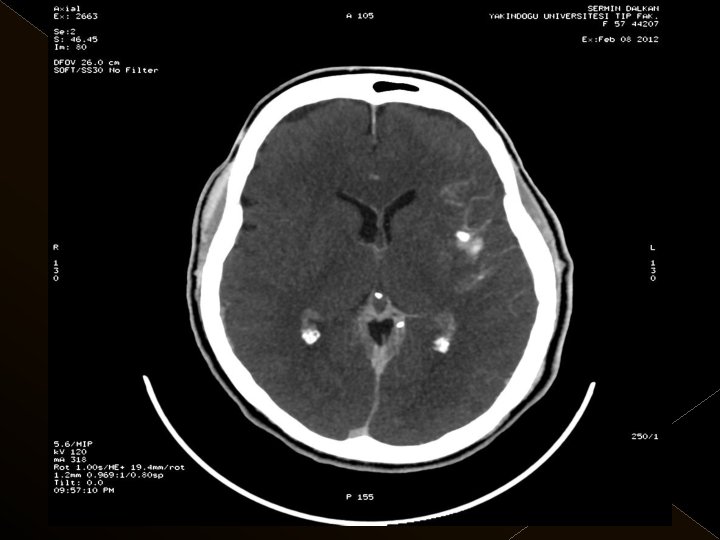

Görüntüleme İşlem öncesi § Bazal kontrastsız BT § BT anjiografi (varsa perfüzyon BT ) § MR (DW, ADC) İşlem sonrası § MR ( DW, ADC, SWI) § 24. saatte kontrol BT veya MR

KOMPLİKASYONLAR Ponksiyon bölgesi komplikasyonları � Trombektomi stentine ait komplikasyon (*1) � Diseksiyon(*2) � Karotikokavernöz fistül (‘ 1) � Hemorajik komplikasyonlar(‘ 5) Semptomatik-nonsemptomatik � İskemik komplikasyonlar (3) � Reoklüzyon (2 i. a) � Kontrast madde nefropatisi �